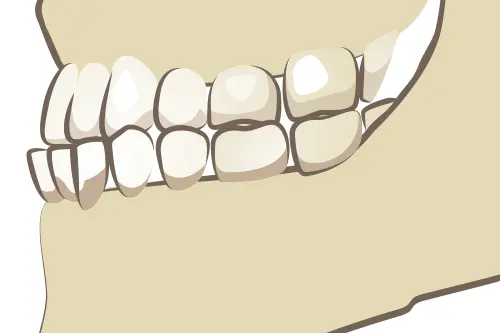

骨格的な問題が原因となっている

上顎と下顎の大きさに極端な差がある、あるいは顎の位置が左右にズレているといった骨格的な問題が背景にある場合、マウスピース矯正単独での治療は困難です。

骨格のズレを治すには、外科手術を伴う外科的矯正治療が必要になることもあります。また、骨格的なズレをカバーしながら歯並びだけを整える「カモフラージュ矯正」を行う場合でも、歯の移動距離が大きくなるため、ワイヤー矯正の方が効率的かつ確実なケースが多いのが実情です。

骨格のイメージ